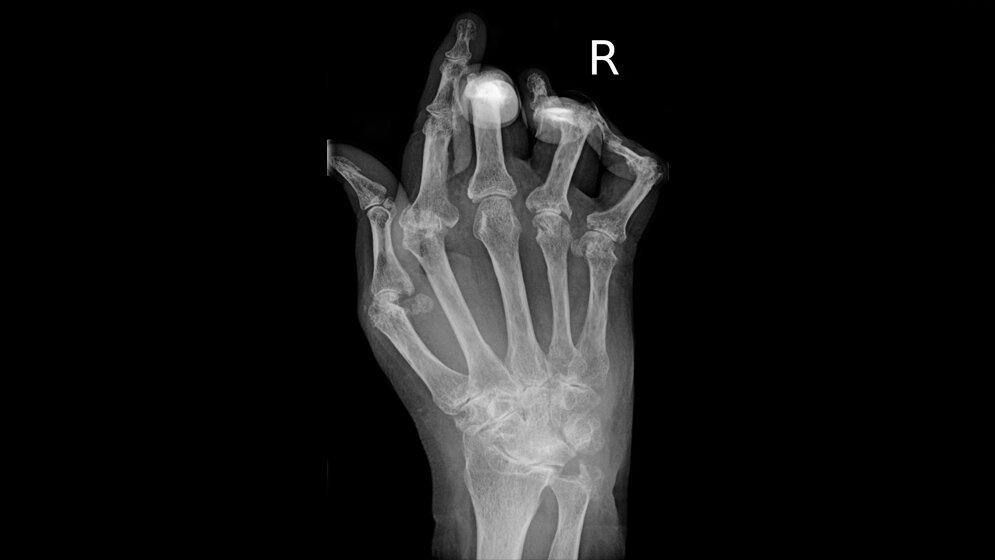

Mehr als eine halbe Million Menschen in Deutschland leiden unter entzündlichem Gelenkrheuma (rheumatoide Arthritis [RA]). Am Anfang der Erkrankung, die meist nach dem 50. Lebensjahr beginnt, stehen Schmerzen und Schwellungen einzelner Gelenke, die sich in den Morgenstunden kaum bewegen lassen. Die Erkrankung wird durch eine Fehlreaktion des Immunsystems ausgelöst. Medikamente, die das Immunsystem bremsen, können eine Zerstörung der Gelenke verhindern.